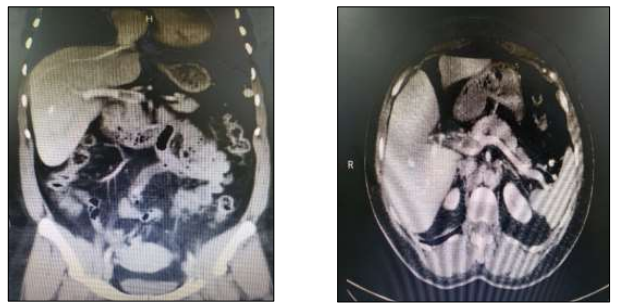

Paciente,sexo feminino, 33 anos, tabagista, apresenta quadro de dor abdominal difusa associada a náuseas e leve distensão abdominal.Nega episódios e cirurgias prévias. Ao exame físico: bom estado geral; hidratada; FC: 85 bpm; PA: 110 x 72 mmHg; FR: 18 irpm; abdômen globoso; RHA+; flácido; e,sem sinais de peritonite; doloroso à palpação profunda de região mesogástrica. Exames laboratoriais sem alterações. Realizada tomografia de abdômen total com contraste:

Enunciado 3265185-1

Além de medidas de suporte, a conduta terapêutica considerada de primeira linha é: